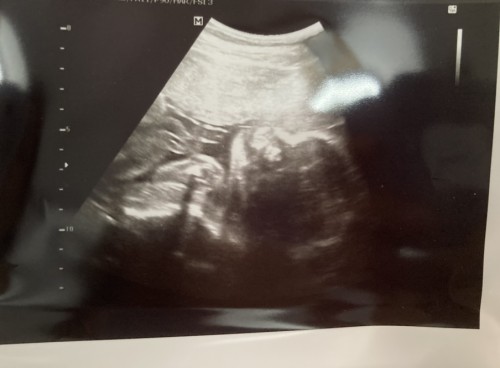

23 สัปดาห์ 3 วัน

คุณหมอบอกน้ำหนักลูกในท้อง 574 กรัมค่ะ อยากรู้แม่ๆ ท่านอื่นที่อายุครรภ์ ไกล้ๆ กัน ลูกน้ำหนักเท่าไรกันบ้างคะ